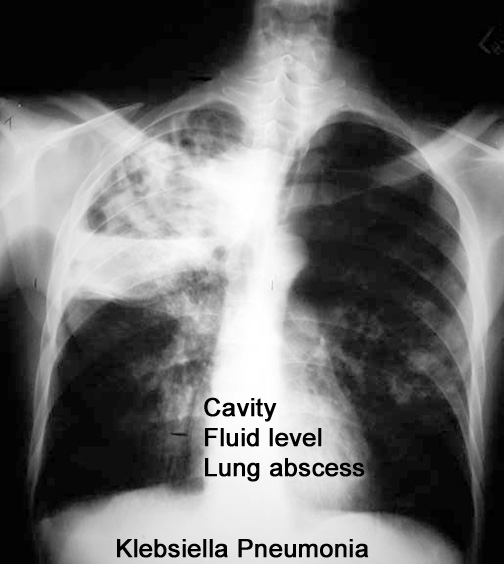

Case 20 Labeled Image List organisms causing necrotizing pneumonia leading to cavitation.